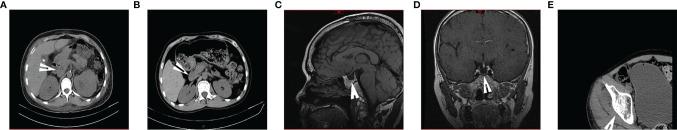

Woodhouse-Sakati syndrome (WSS) (OMIM#241080) is a rare multi-system autosomal recessive disease with homozygous mutation of the DCAF17 gene. The main features of WSS include diabetes, hypogonadism, alopecia, deafness, intellectual disability and progressive extrapyramidal syndrome. We identified a WSS family with a novel DCAF17 gene mutation type in China. Two unconsanguineous siblings from the Chinese Han family exhibiting signs and symptoms of Woodhouse-Sakati syndrome were presented for evaluation. Whole-exome sequencing revealed a homozygous deletion NM_025000.4:c.1488_1489delAG in the DCAF17 gene, which resulted in a frameshift mutation that led to stop codon formation. We found that the two patients exhibited low insulin and C-peptide release after glucose stimulation by insulin and C-peptide release tests. These findings indicate that the DCAF17 gene mutation may cause pancreatic β cell functional impairment and contribute to the development of diabetes.